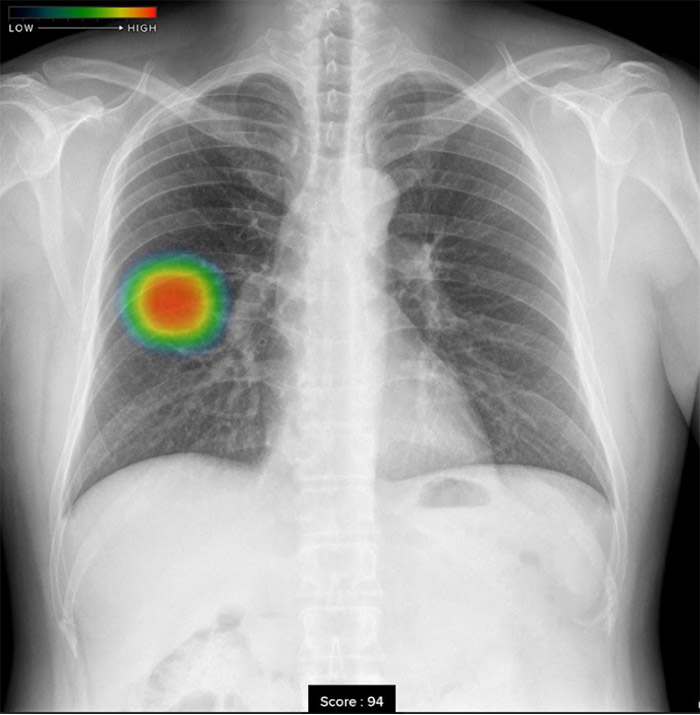

胸部レントゲン検査の場合、見る医師が少しでも異常がありそうと判断をしたら「要精査」とコメントし精密検査を行う流れになります。見落としがないように少しでも異常が疑われればやや過剰にでも異常と判断をいたします。そこでエルフ内科クリニックでは最新のAI技術を活用し、病変検出能が明らかに向上する「胸部X線画像病変検出ソフトウエアCXR-AID」を導入いたしました。

撮影画像を自動解析して、結節、腫瘤影、浸潤影、気胸が疑われる領域を検出しマーキングいたしますので、医師とAIがダブルチェックを行ない、診断精度を高めております。

• 結節・腫瘤影結節・腫瘤影